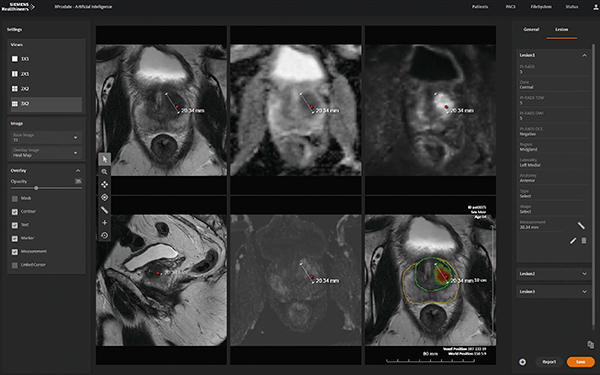

また,前立腺がんに対する診断支援ツールも開発している。PSA検査など,スクリーニング検査によって前立腺がんの疑いがある場合,鑑別診断の手段の一つとして,MRIによる画像診断が行われている。マルチパラメトリックMRI画像よりPI-RADSスコアリングを行うことによって,患者の予後に影響があるような“臨床的に意義のあるがん”を検出する3)。このマルチパラメトリックMRI画像に対し,前立腺病変を自動的に検出し,PI-RADSスコアを提案する診断支援ツールを開発している(図2)。

図2 マルチパラメトリックMRI画像に対するAI画像診断支援ソフトウエアの解析結果例

赤いランドマーク,あるいは右下の画像のヒートマップが病変部を示す。